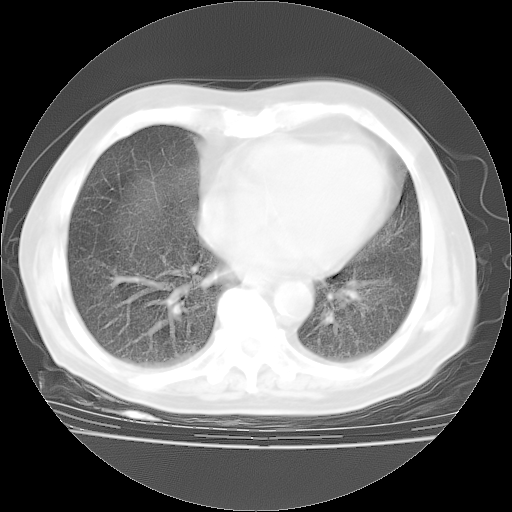

4月28日肺部CT——再次出现类似去年5月9日——透光度降低,“间质性”改变。

4月28日肺部CT——再次出现类似去年5月9日——磨玻璃样、间有“粟粒样”改变。

个人阅读4.14日肺部CT平扫:纵隔窗无异常,但肺窗示:双下肺内、后基底段有片絮状侵润影,部位以后基底段为著,以间质改变为主,呈急性肺泡炎征像,和首次住院影像学有相似之处。仅是个人读片,明日请相关专家再读片哈。其它建议同上。

今请临免主任会诊后认为:4月14日胸部CT已有双下肺间质性改变。患者病情复发多系激素减量过快不正规所致。目前甲强龙80mg/日,一周后酌情开始减量,不易过快。环磷酰胺若已停用,暂不使用。他同意目前抗菌药物使用,但应考虑是否加用B-内酰胺类抗菌药物(中性细胞明显增高);2、结核复发目前依据不足;3、若免疫全套各项指标正常,考虑多系特发性肺间质炎可能大。4、加强支持,并注意保护胃黏膜。